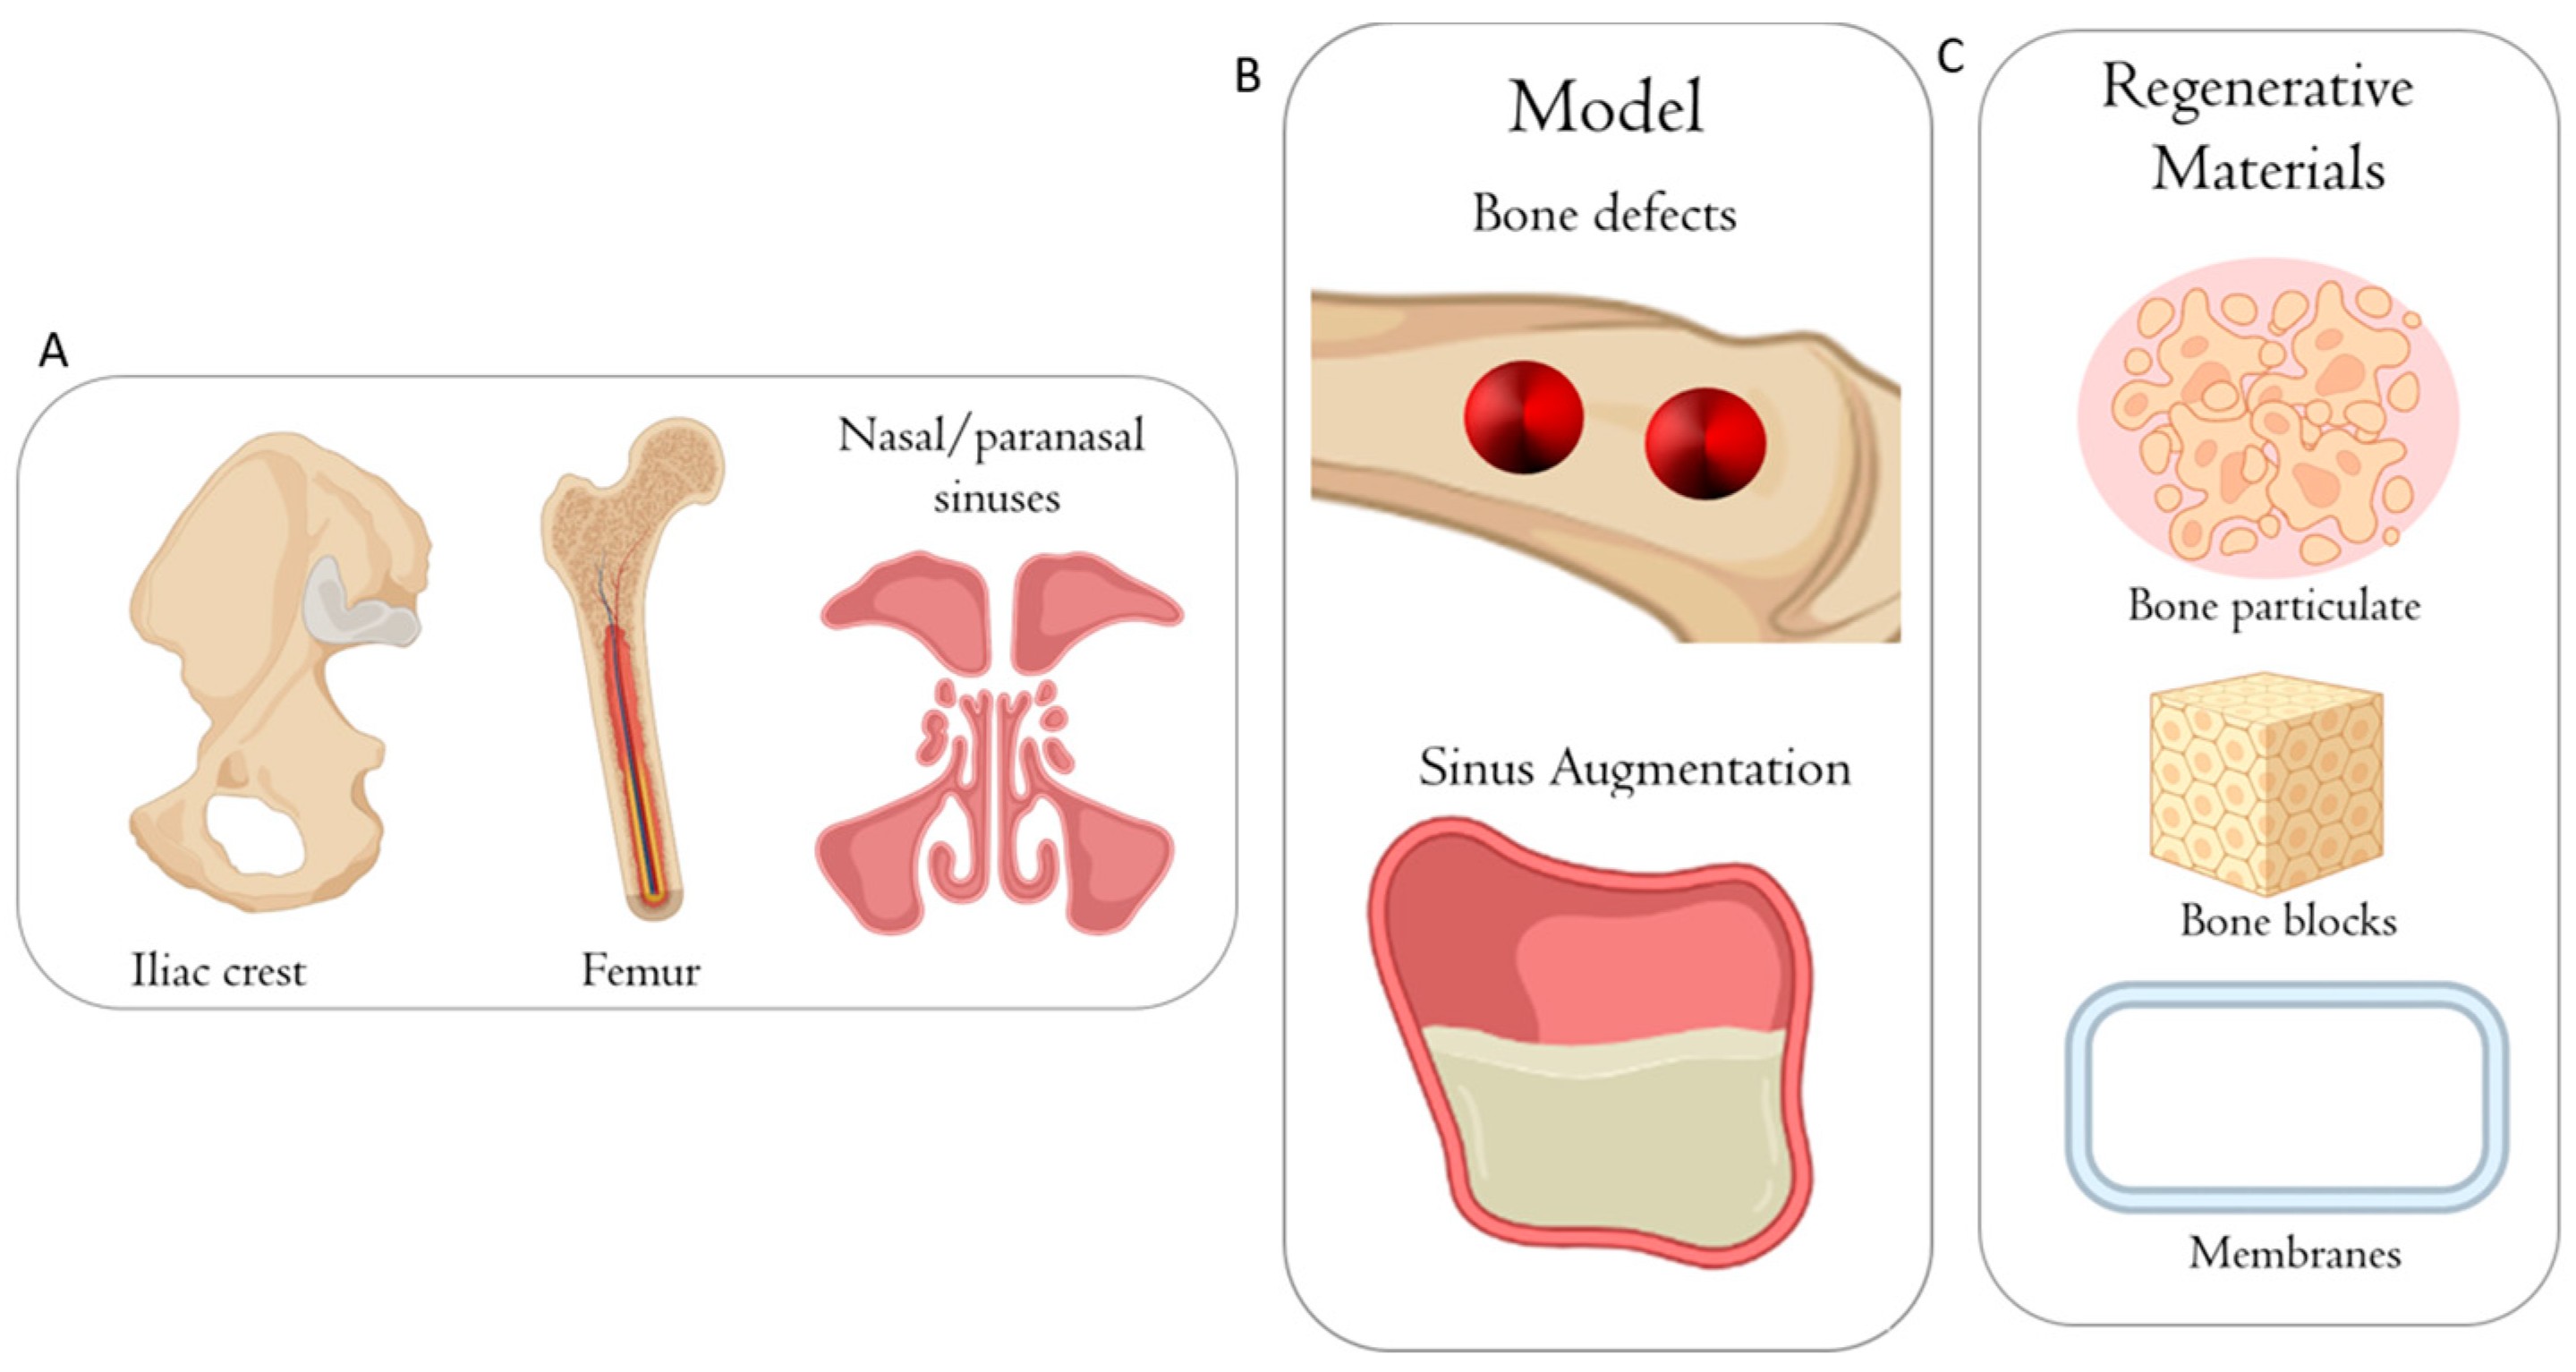

2. Use of Animal Models in Pre-Clinical Research

3. Small Animal Models

4. Large Animal Models